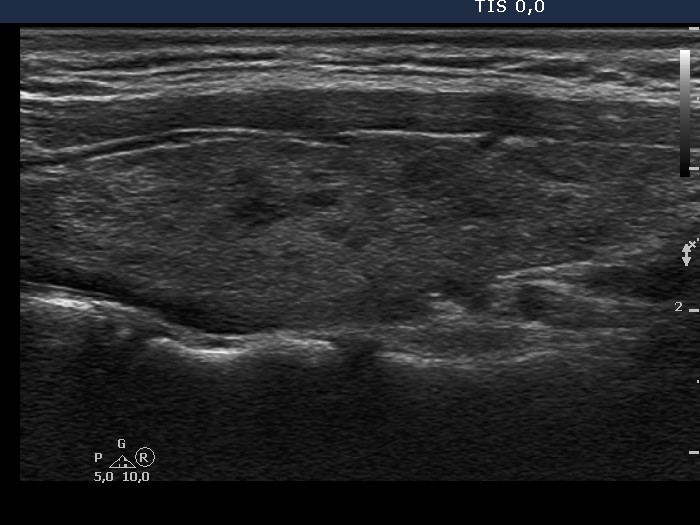

Ultrasonography: the thyroids were echonormal and contained around 15% hypoechogenic areas. The vascularization was minimally increased.